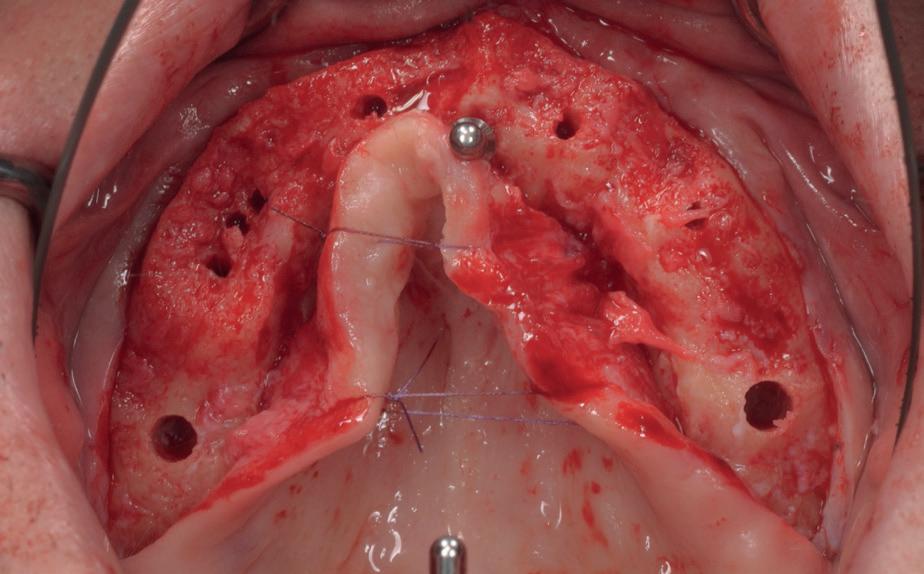

Voor de behandeling kreeg de patiënt Amoxicilline 500mg 3dd1 gedurende een week voorgeschreven waarbij er een dag voor de chirurgie gestart werd, als pijnstilling Ibuprofen 600 mg 3dd1 voor een week en Blue M Mouthwash voor de mondspoeling gedurende de eerste 2 weken. Na de anesthesie werd een incisie gemaakt van tuber tot tuber en werd de

3. Na flap een guide pin in foramen incisivum

4. Plaatsen van 6 implantaten en kaakverbreding 14

5. Primaire sluiting met een door-

mucosa zowel buccaal als palatinaal afgeschoven. Het is belangrijk om te realiseren dat de bovenkaak zachter alveolair bot heeft dan de onderkaak en dat stug periost op de kaak kan zitten. Daarom is het van belang om te starten met curettage van de kaak. Na het vrijleggen van de canalis incisivum, werd een guide pin in de canalis geplaatst. Het kanaal loopt loodrecht op de kaak en kan dienen als referentie

lopende hechting

6. Tweede fase chirurgie

voor de implantaten (afbeelding 3). Hierna werd met een meetinstrument de locaties van de implantaten uitgemeten en werd een initiële osteotomie op deze locaties gemaakt. Voor de 16 werd een crestale sinusbodemelevatie met Densah boren uitgevoerd. Hierbij werd het zachte bot gecondenseerd om naar crestaal geduwd te worden, waarna het membraan van Schneider meelifte. Door de osteotomie werden 1cc botkorrels geplaatst en daarna direct het implantaat. Ter plaatse van de 14 zat een verticaal botdefect, na plaatsen van dit implantaat, werd de kaak verticaal verhoogd. Er werden 6 implantaten van het merk AnyRidge (MegaGen Implant Company, Korea) geplaatst met diameter 5.0 mm aan de distale zijdes, diameter 4.5 mm bij de premolaren en 4.0 mm implantaten bij de laterale incisieven (afbeelding 4).

Ter plaatste van de 16 en 14 werden verticale matrashechtingen geplaatst, waarna er één doorlopende hechtingen van tuber tot tuber volgde met een 4-0 gevlochten hechtdraad (afbeelding 5). Gedurende de eerste 2 weken van de genezing is het van essentieel belang voor de wondgenezing, dat de patient geen bovenprothese draagt. Deze werd daarom ingenomen, met de uitleg dat direct dragen van de bovenprothese een nadelige invloed heeft op de genezing van de kaak, de botopbouw en de implantaten. Patiënt kwam 2 weken na de chirurgie retour voor het verwijderen van de hechtingen, waarna de binnenzijde van de bovenprothese werd uitgeslepen en voorzien werd van een softliner als nieuwe tijdelijke voering voor retentie van de bovenprothese. Vanwege de kaakverhoging en sinusbodemelevatie, werd 6 maanden genezing afgewacht van het bot en integratie van de implantaten.